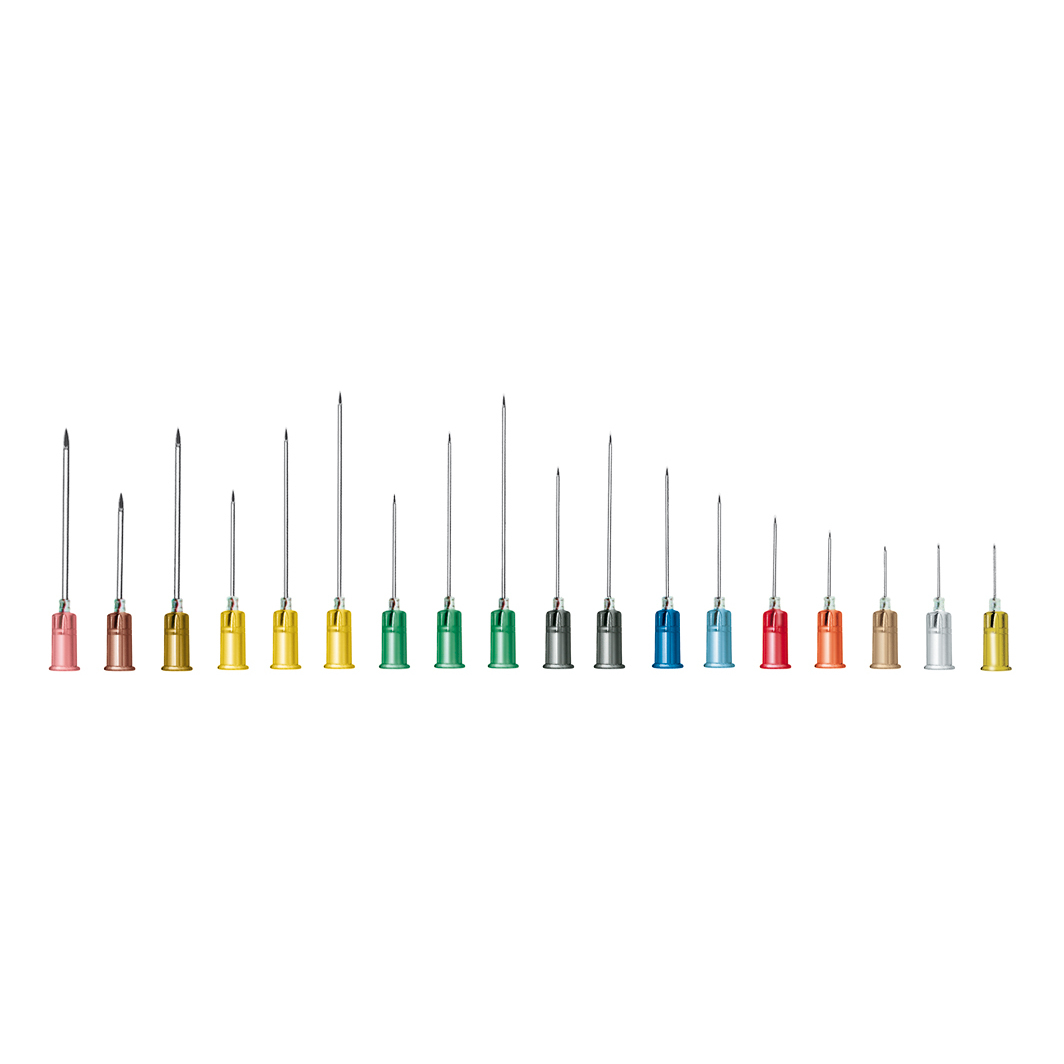

Aghi monouso misure e codici: - g18 (rosa): 00282; - g19 (marrone): 00284; - g20 n.

1 (giallo): 00285; - g21 n.

2 (verde): 00286; - g22 n.

12 (nero): 00288; - g23 n.

14 (blu): 00290; - g23 n.

16 (azzurro): 00291; - g25 (arancio): 00292; - g26 (nocciola): 00294; - g27 (grigio): 00295; - g30 (neutro): 00298.

| Codici | g18 (rosa)00282 |

|---|---|

| - g19 (marrone) | 00284 |

| - g20 n.1 (giallo) | 00285 |

| - g21 n.2 (verde) | 00286 |

| - g22 n.12 (nero) | 00288 |

| - g23 n.14 (blu) | 00290 |

| - g23 n.16 (azzurro) | 00291 |

| - g25 (arancio) | 00292 |

| - g26 (nocciola) | 00294 |

| - g27 (grigio) | 00295 |

| - g30 (neutro) | 00298 |